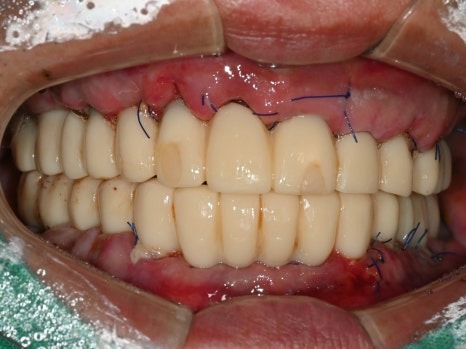

수술 당일

수술 2일 후

직장에서 시간을 내기가 어려우신 상황이라

토요일 오전,

수면마취로 17개의 임플란트를 식립하였고,

월요일에 임플란트 즉시 기능 치아(임시치아)를 끼워드렸습니다.